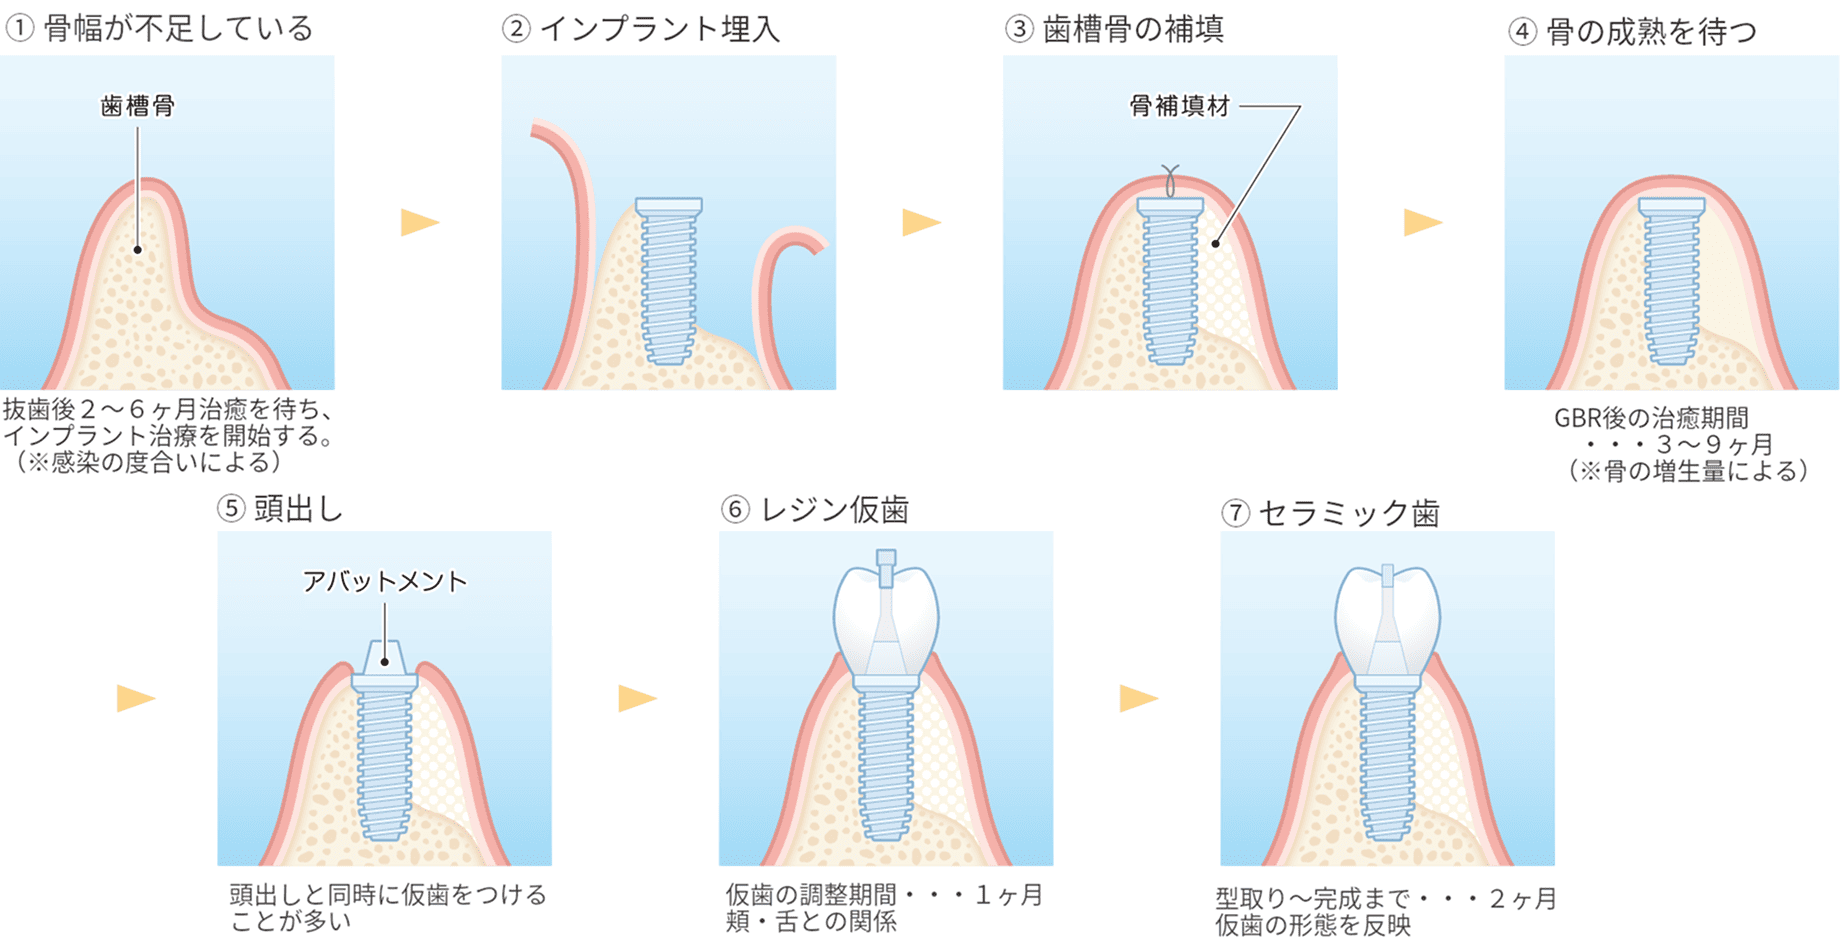

代表的な再生療法のひとつが「GBR(骨誘導再生法)」です。骨が不足した部位に自家骨や人工骨を補填し、特殊な膜(メンブレン)で覆うことで、骨の再生を促しインプラントの土台を築く方法です。